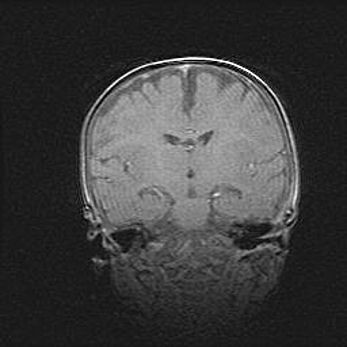

Множественные кисты обоих полушарий головного мозга, наибольшая из них в правой затылочной области. Ассиметричная атрофическая гидроцефалия.

Возраст: 7 месяцев

Вес: 5660 г

Пол: мужской

Окружность головы: 41,5 см

Срок гестации: 28-29 недель

Кисты головного мозга развиваются в результате многоочаговых некрозов вещества мозга и возникают вследствие перенесенной перинатальной инфекции, менингитов, энцефалитов, асфиксии, родовой травмы, расстройств мозгового кровообращения различного генеза. Образованию кист в веществе головного мозга плодов и новорожденных способствуют такие факторы, как высокое содержание в нем воды, недостаточная (или отсутствие) миелинизация и слабая астроглиальная реакция на повреждение.

Кисты могут сочетаться с гидроцефалией и другими поражениями головного мозга.